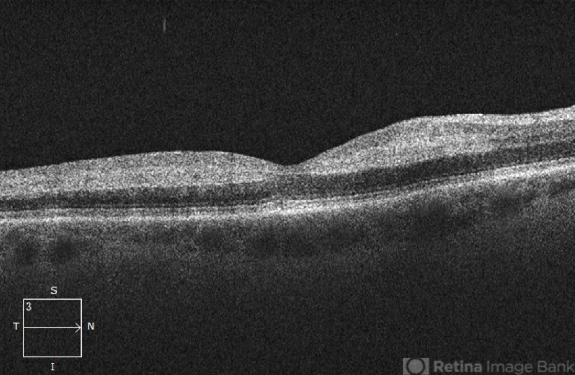

- BRAO, branch retinal artery occlusion (BRAO)

- OCT